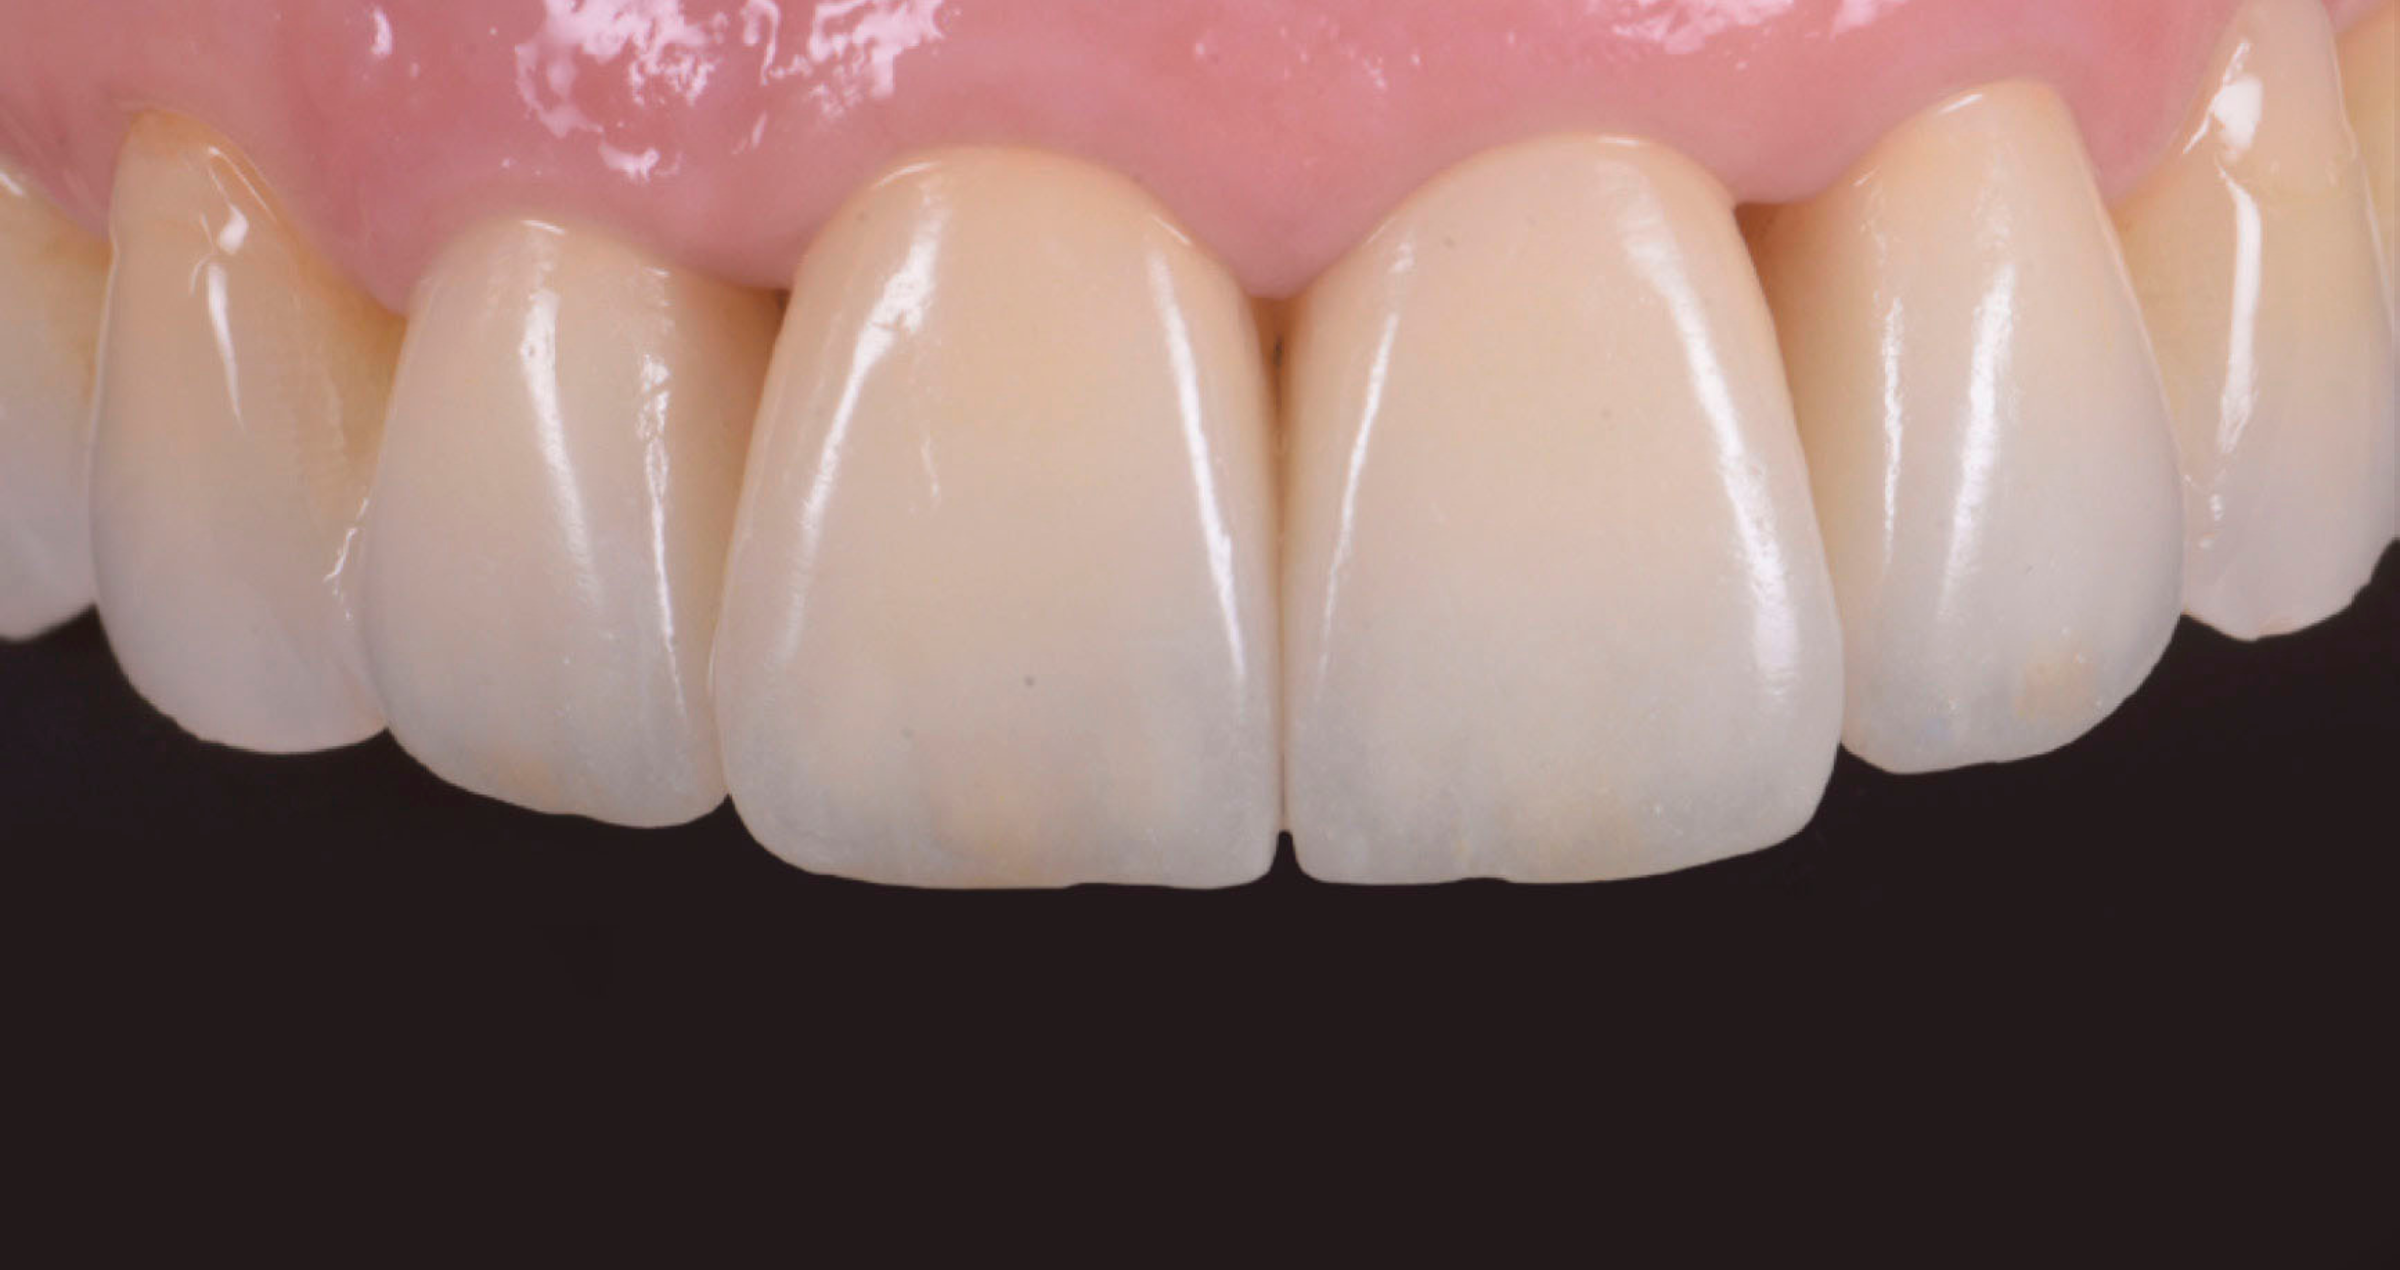

La tecnica di Internal Stain ha previsto l’applicazione di ceramiche colorate specifiche direttamente sulla superficie della zirconia, prima della stratificazione, per personalizzare cromaticamente le faccette, replicando le sfumature naturali del dente e migliorando l’integrazione estetica con i denti adiacenti. Successivamente, la micro-stratificazione con CZR con tecnica 4.4.1. è stata eseguita con strati sottili di smalti Luster, applicati in modo selettivo, per ottimizzare la traslucenza e la resa estetica vestibolare senza compromettere la resistenza strutturale. Questo approccio ha permesso di ottenere un risultato altamente estetico, con una chiusura efficace dei diastemi e un’armonizzazione del sorriso, mantenendo uno spessore protesico ridotto e un’integrazione naturale con i tessuti parodontali.

Fig. 6: Situazione finale della paziente con integrazione funzionale ed estetica dei restauri.

A 6 mesi dalla cementazione, le faccette mostrano un’eccellente integrazione estetica, stabilità cromatica e buona risposta dei tessuti parodontali.

Le faccette in zirconia cubica stratificata KATANA Zirconia YML combinano resistenza strutturale e resa estetica elevata, rendendole ideali in casi clinici in cui sia necessario bilanciare esigenze funzionali e richieste estetiche. Il design minimamente invasivo e la progettazione digitale sono fondamentali per il successo a lungo termine.

Il caso dimostra l’efficacia dell’impiego di faccette in zirconia cubica stratificata KATANA Zirconia nella riabilitazione estetica del settore anteriore, soprattutto in presenza di diastemi post-parodontali e restauri preesistenti.